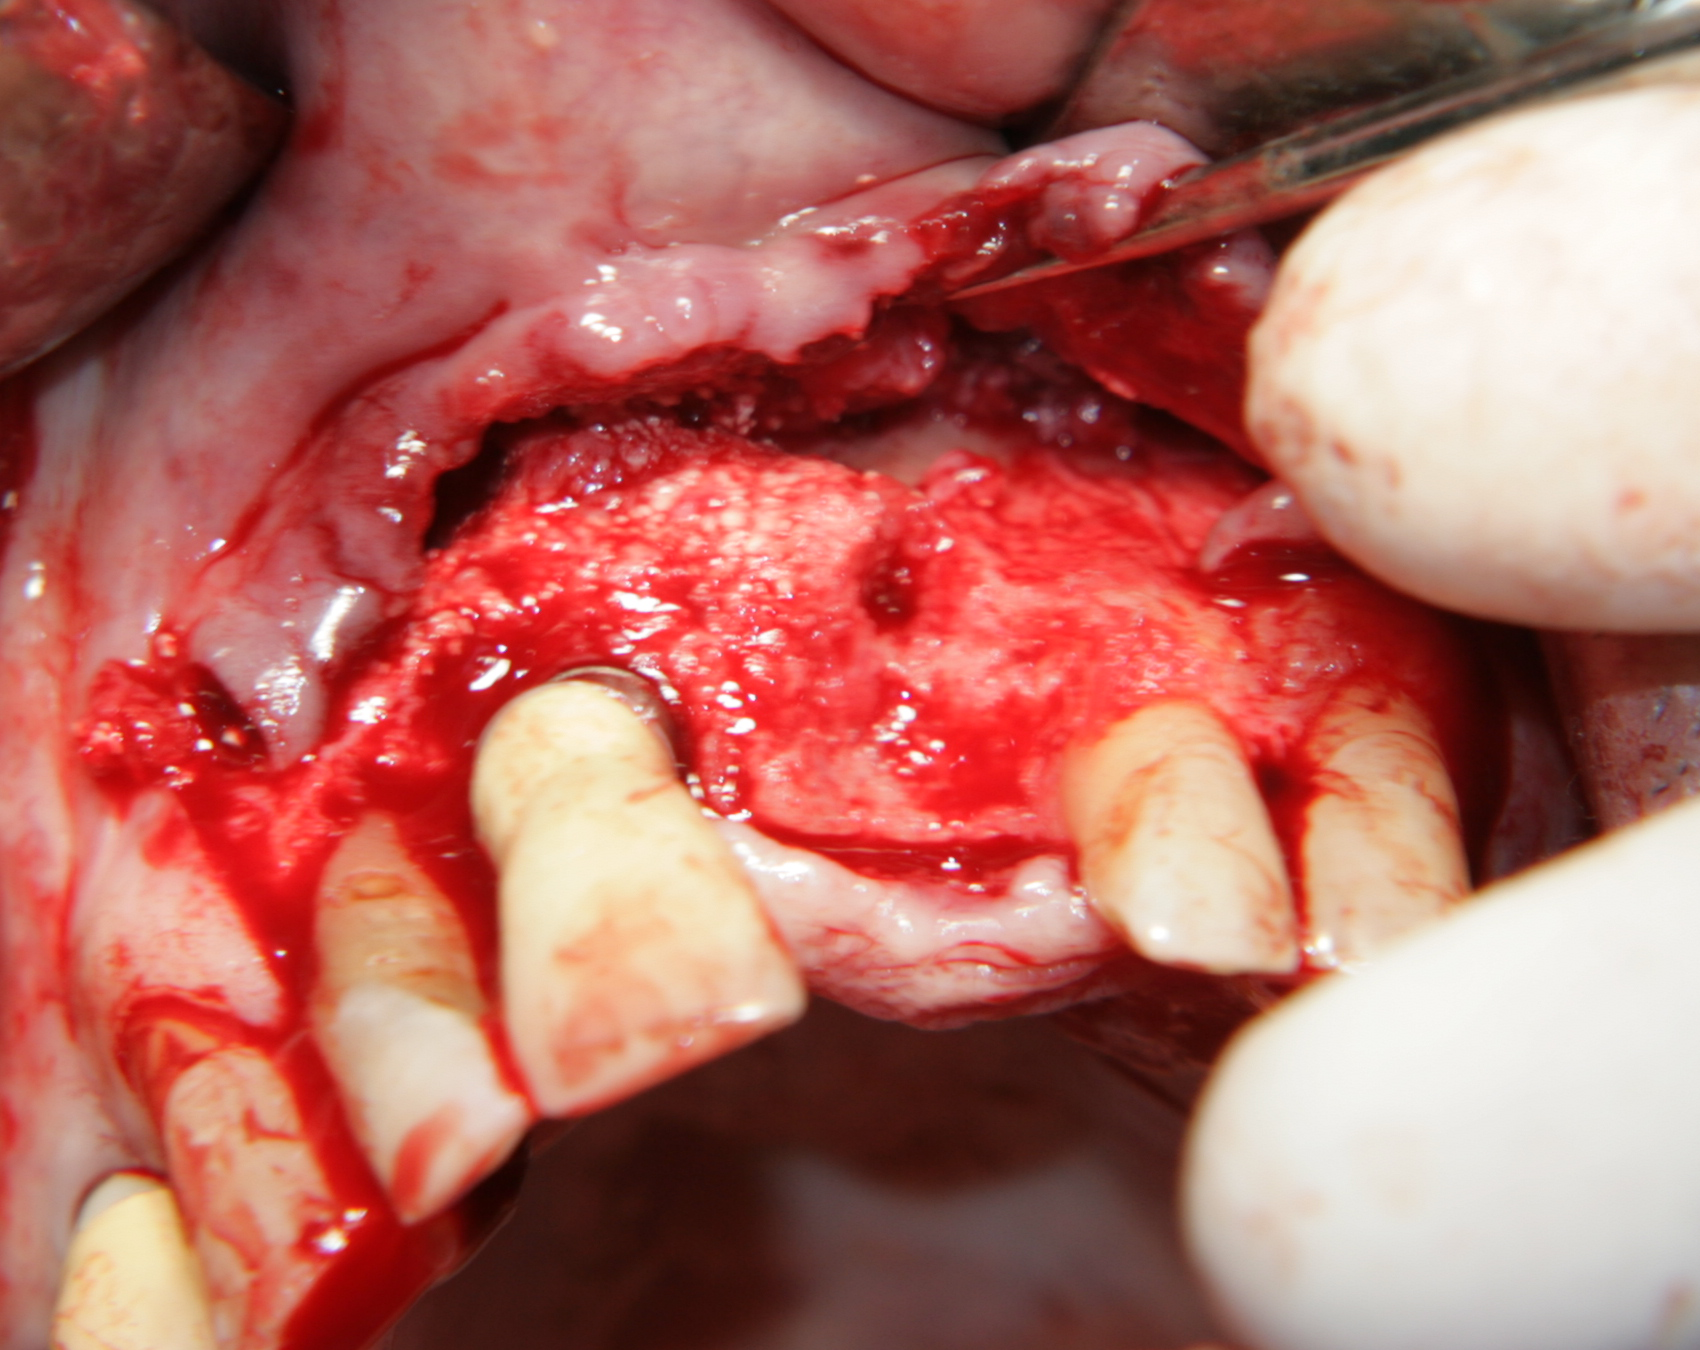

На горната снимка се вижда зъб, който подлежи на екстракция. Подвижен, болезнен при дъвчене, с наличен дълбок пародонтален джоб, от който изтича постоянна ексудация. Въпреки отличните резултати, за които съобщават всички поддръжници на пародонталната хирургия, нашият екип прецени настоящия зъб като безперспективен за пародонтална хирургична намеса. В резултат на това зъбът беше екстрахиран и по бързата процедура предаден на студенти - третокурсници за практическите им занятия по ендодонтия. Всичко това се случи през месец октомври 2009 година; само шест месеца след това, през месец април 2010, посетихме една впечатляваща лекция на проф. Авиад Тамзе от Университета в Тел Авив. Въпросният колега изнесе презентация на петнадесетия конгрес на Балканското Стоматологично общество в град Солун и просрочи с двадесет минути определеното му от организационния комитет време. Въпреки че беше краят на деня и всички посетители бяха доста уморени, никой не напусна лекцията - всичко беше крайно интересно... Според професор Тамзе всеки девитализиран зъб с дълбок пародонтален джоб и венечно възпаление от няколко месеца е съмнителен за вертикална фрактура на корена; рискът се увеличава многократно при наличие на метални щифтове или цели пънчета, както е при зъба на горната снимка. Най-вероятно въпросният зъб е имал частична или пълна коренова фрактура - единственото лечение в този случай е екстракцията; според проф. Тамзе е необходимо това да се извърши възможно най-скоро, за да се предпази околната кост от резорбция. Поставянето на имплант непосредствено след изваждането на корена още повече съхранява наличните костни тъкани. От чисто научен интерес проследихме 25 зъба с метални щифтове, които подлежаха на екстракция - при всеки един от тях имаше фрактурна линия с различна конфигурация. Описание на един от тези случаи сме публикували тук...

На тази снимка се вижда зъбната алвеола след изваждането на зъба. Формата на алвеолата е изключително подходяща за имедиатно имплантиране - кръгла, без междукоренови прегради, с добре запазени костни стени. Вестибуларно се вижда костен израстък, който бързо би се лизирал ако не се постави имплантат - всяка структура в организма, която не е подложена на функционално натоварване, започва да атрофира много бързо. Поради това всички автори в световната литература са единодушни за един факт: имедиатното имплантиране предпазва от костна загуба поради липсата на време за афункционална атрофия. В този ред на мисли описаният случай на имедиатно имплантиране има много по-добра прогноза, отколкото ако се изчака оздравяването на екстракционната рана.

Меките тъкани са отпрепарирани и зъбът е екстрахиран. Вижда се

обширен костен дефект - почти няма стени, само обширно

хлътване. На мястото на апекса на зъба се вижда остатък от алвеола